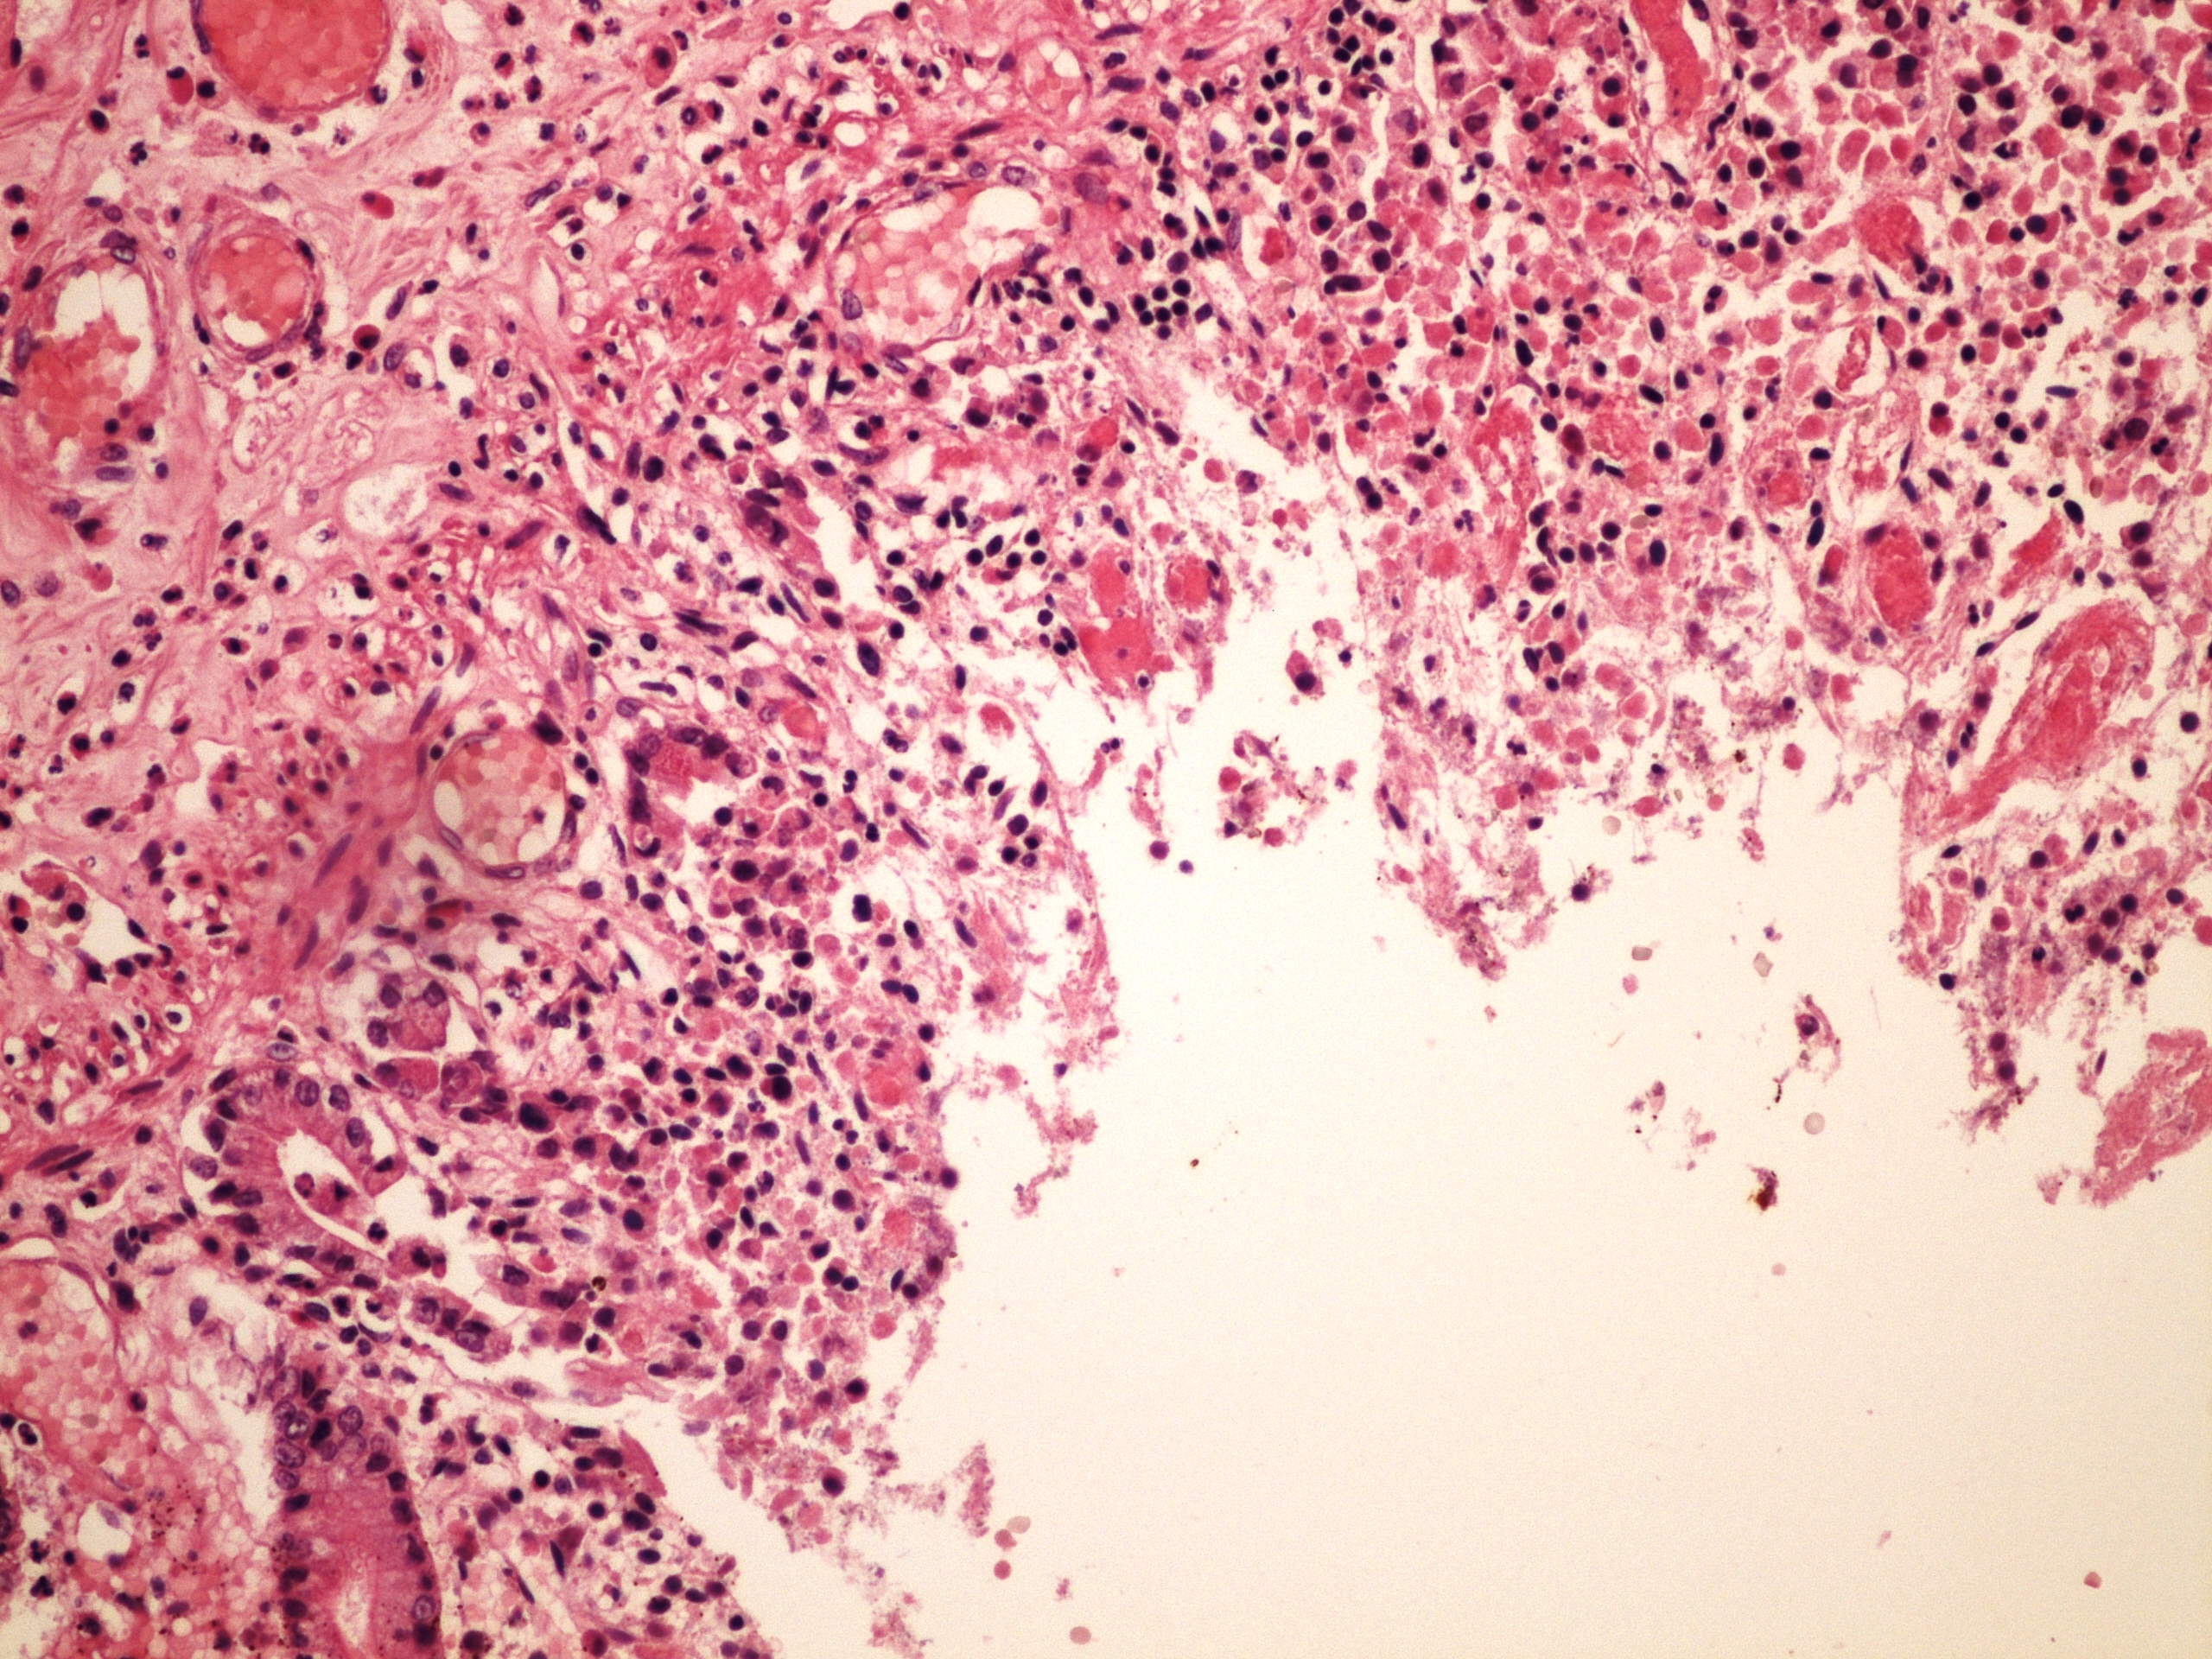

Preparát č.7 a č.8 - kolikvační nekróza

Struktury

- nekróza

- zrnéčková buňka